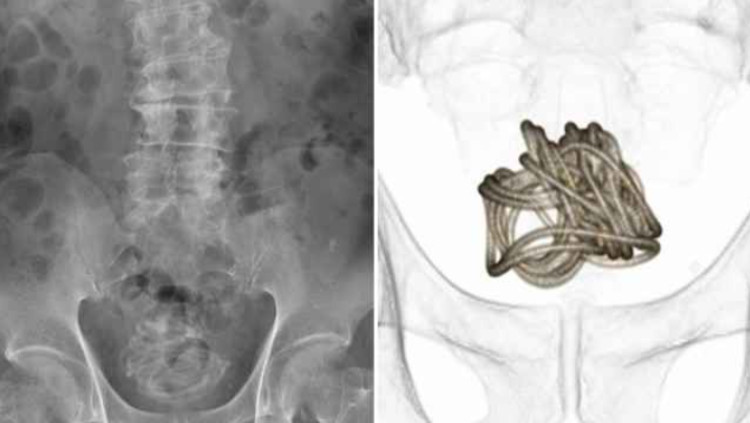

באורך שני מטרים: החדיר חבל מפלסטיק לצינורית השתן שלו - כך זה הסתיים